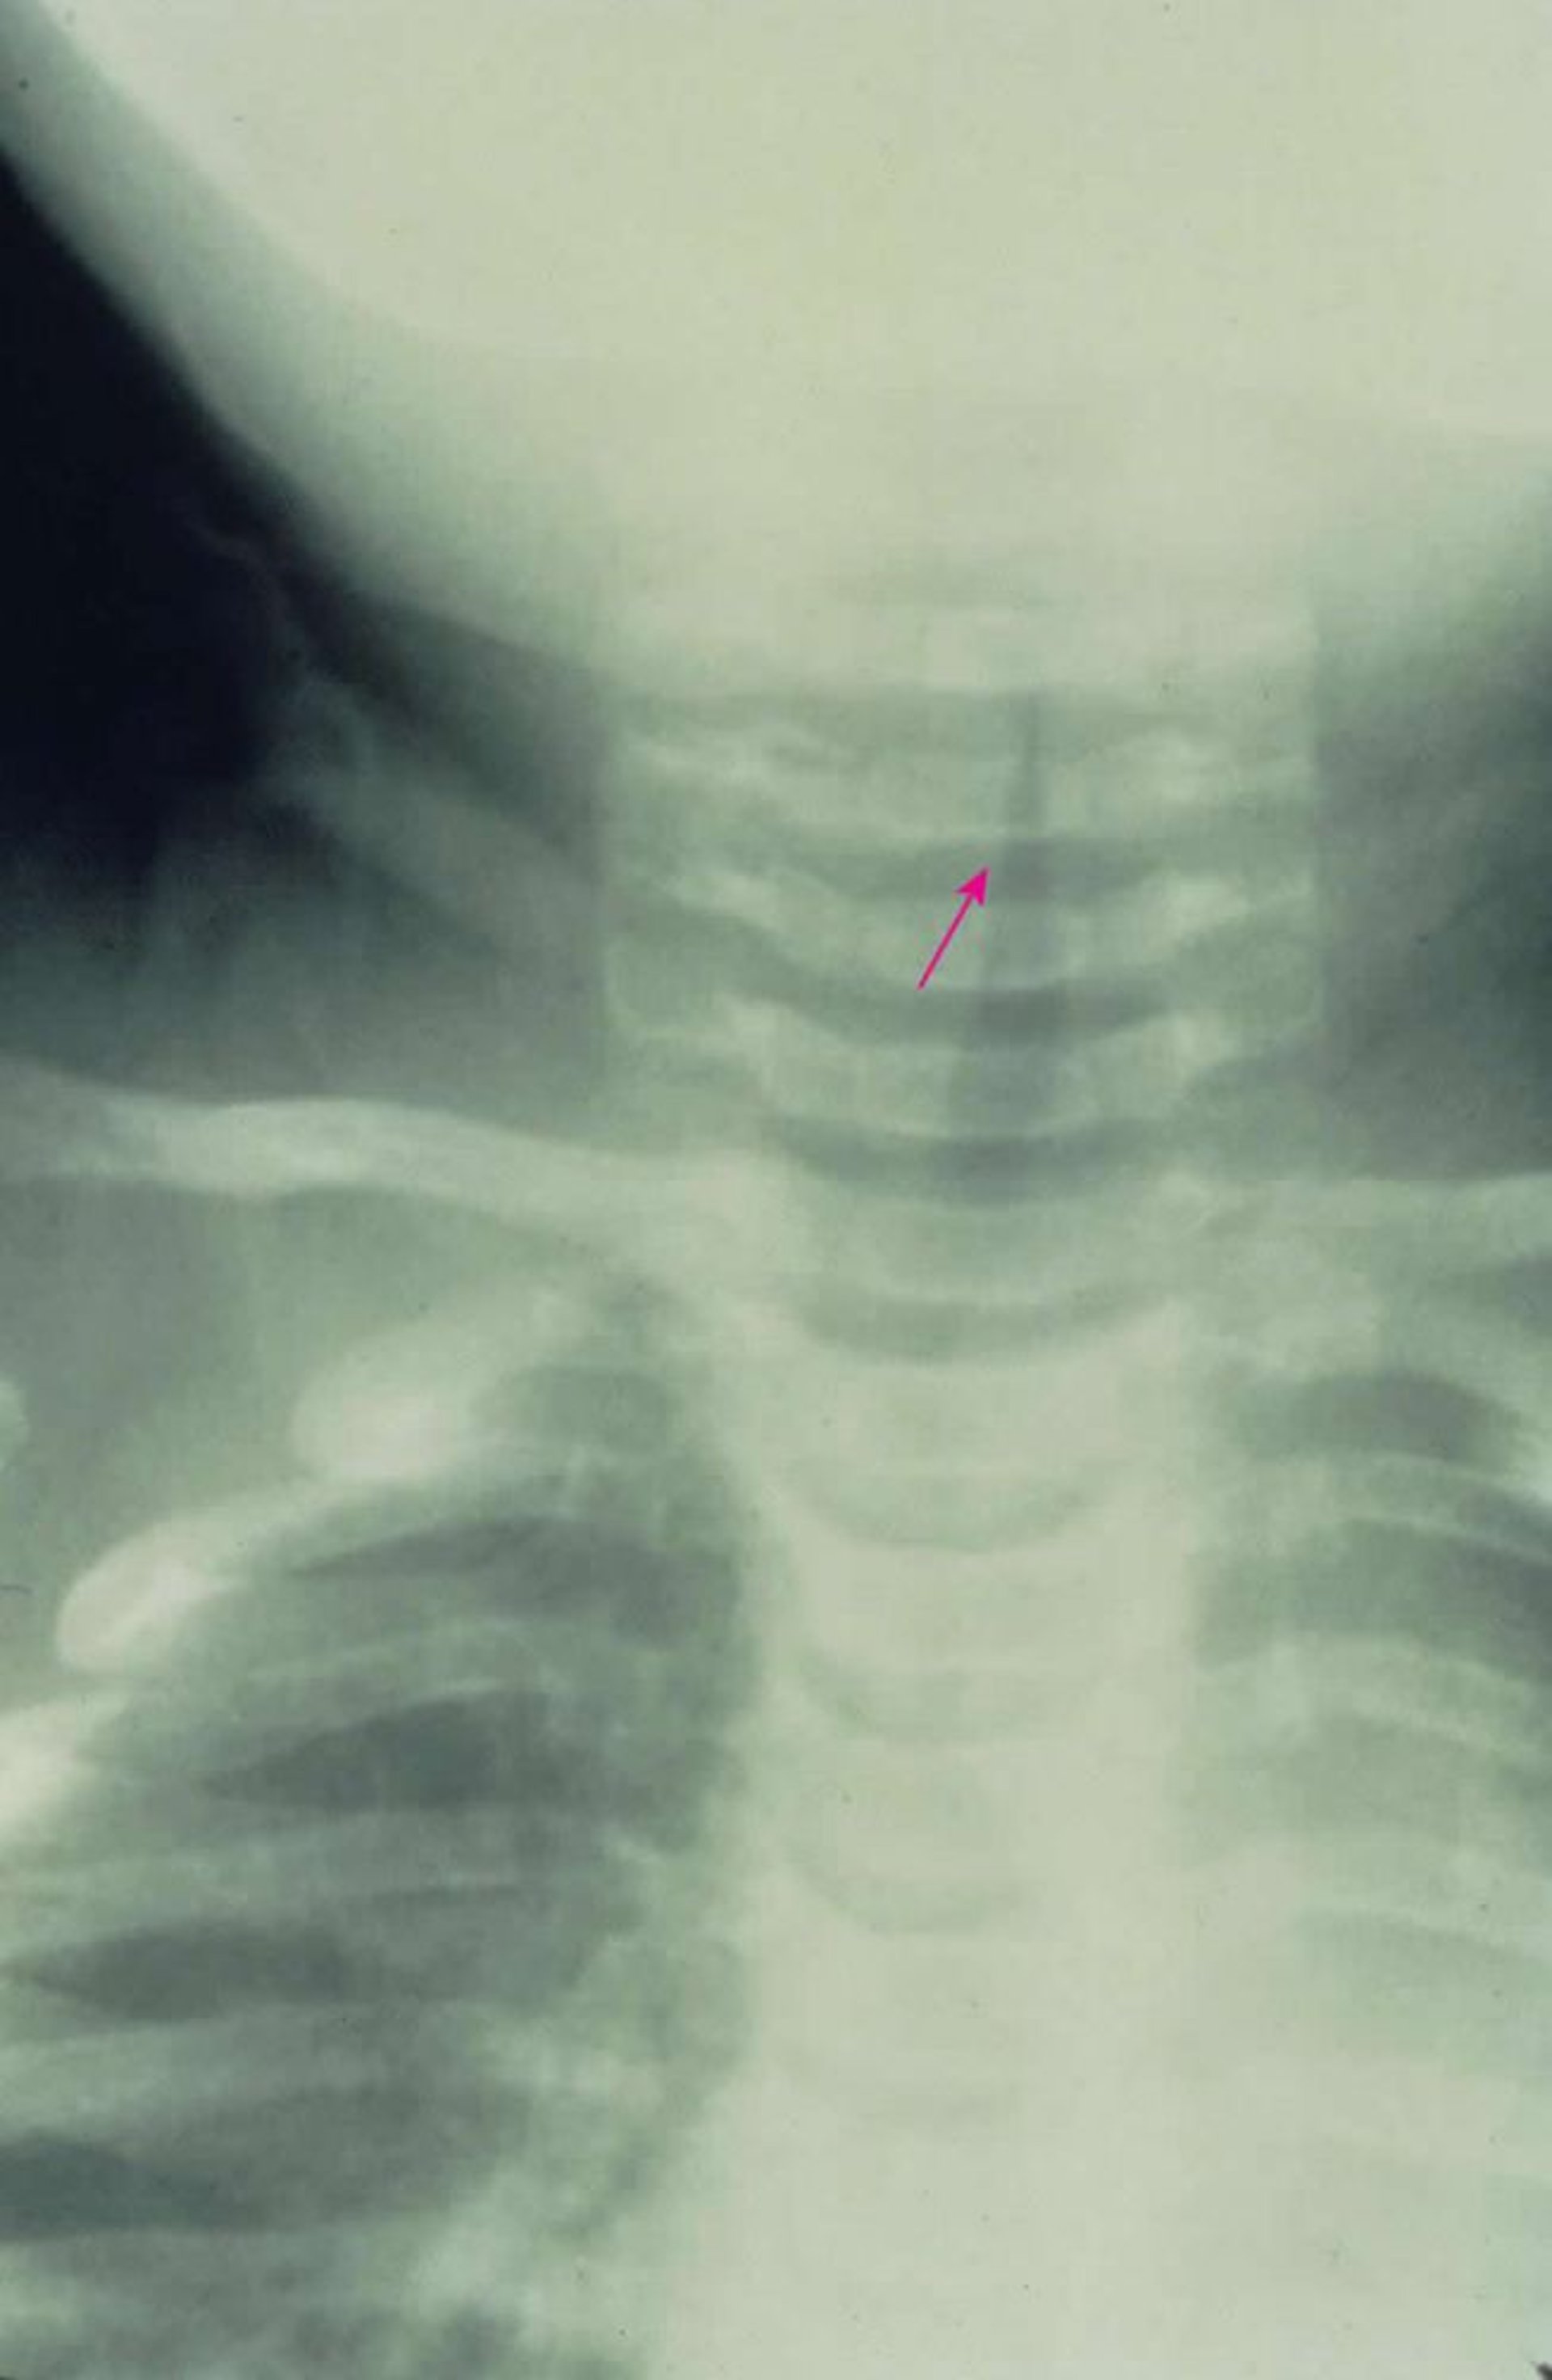

Subglottischer Krupp

Diese anterior-posteriore Röntgenaufnahme zeigt eine charakteristische subglottische Einengung der Atemwege (Kirchturm-Zeichen [Pfeil]), die durch Krupp verursacht wird.

Image provided by Clarence T. Sasaki, MD.